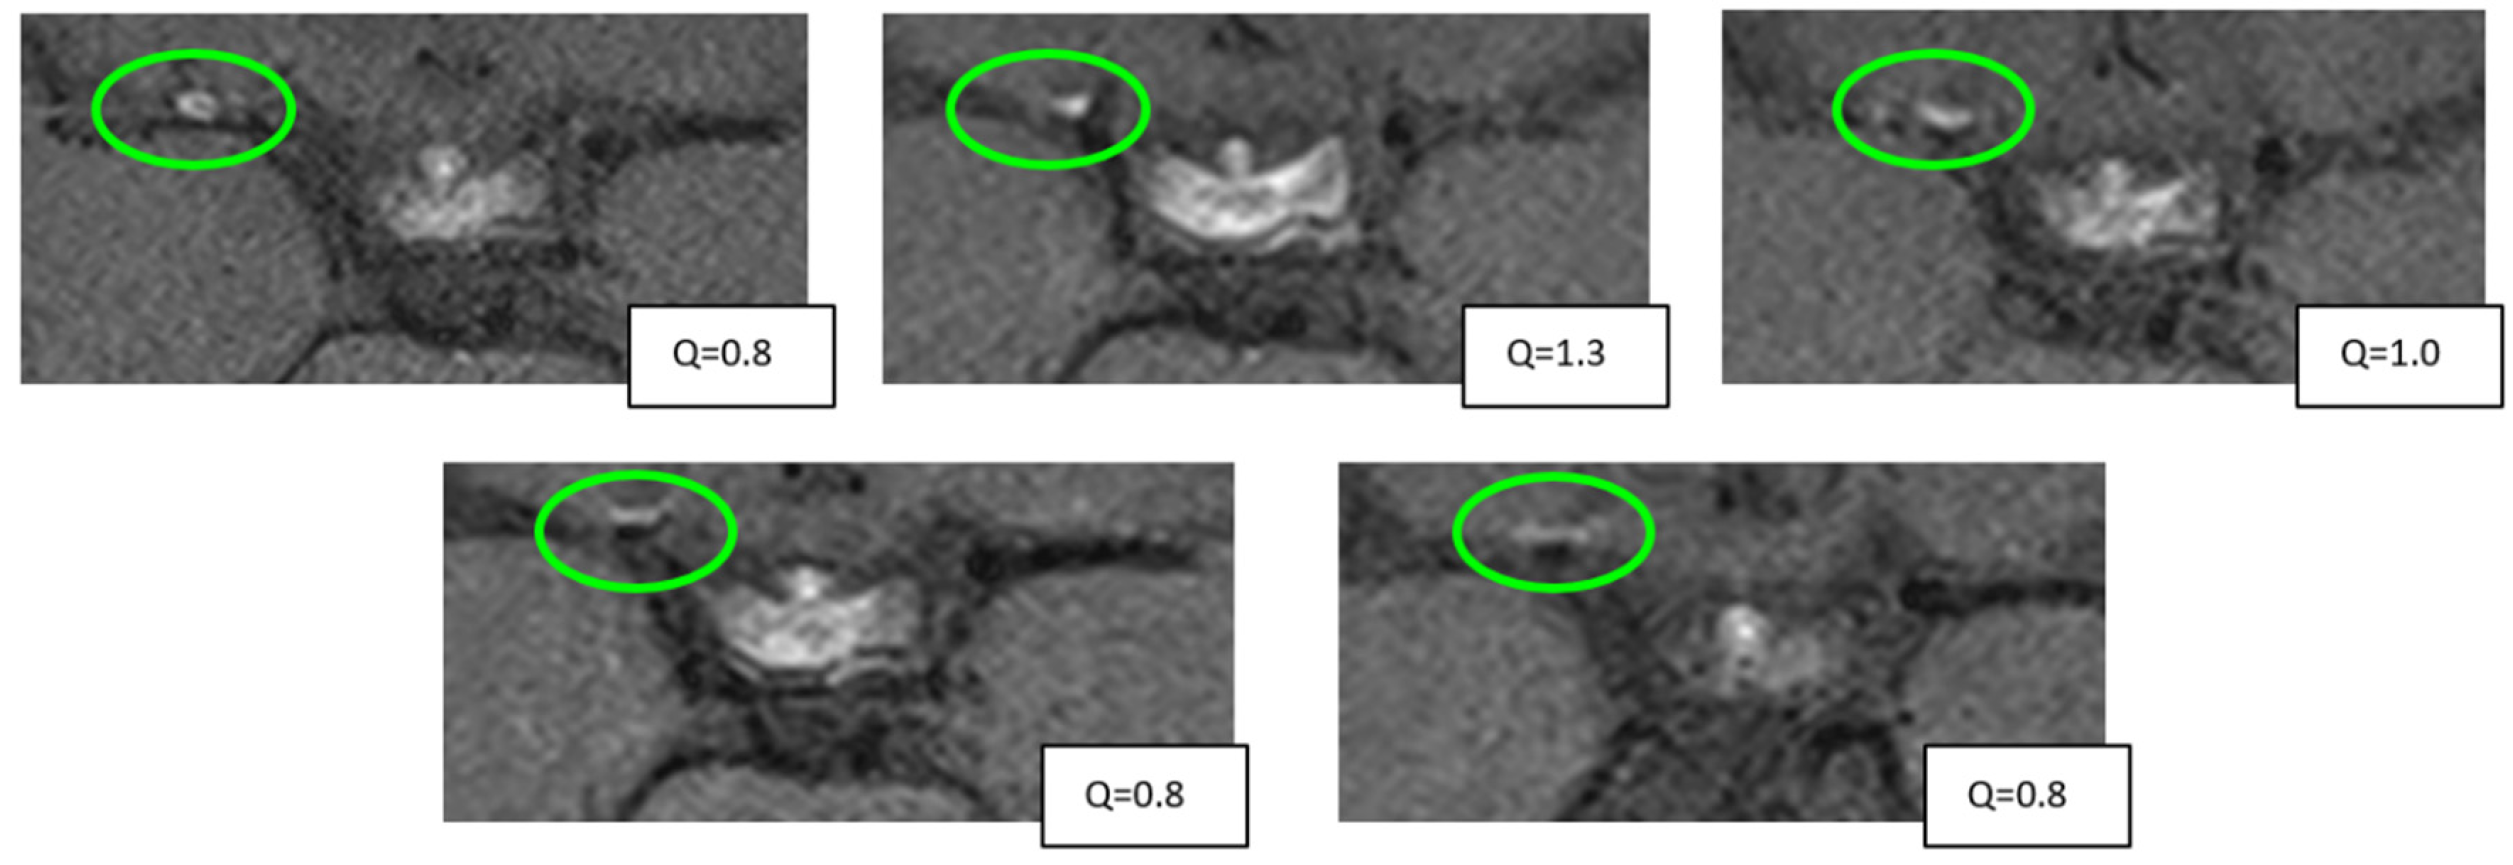

2.3. Measurements

3.5. Vessel Wall CE Dynamics

3.6. Correlation with Stroke, CVR, and Angiographic Stenosis